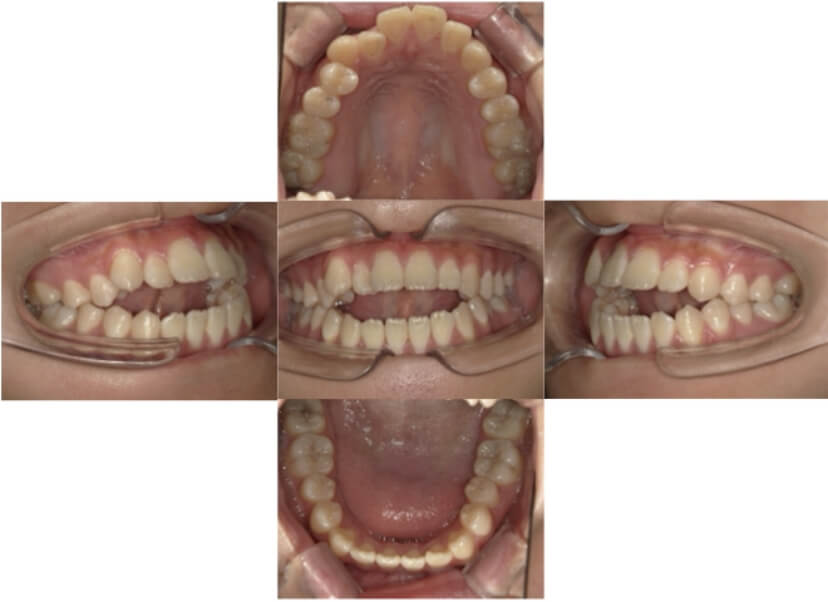

症例2

上下顎前突、叢生

抜歯

ブラケット矯正

上下顎前突、叢生(上下出っ歯、上下の前歯のガタガタ)のケースです。

装置はラビアル(上下表側)で、上下顎の小臼歯を4本抜歯を行っています。抜歯したスペースを使って、上下の前歯の後方移動と叢生(ガタガタ)の改善を行っています。

主訴 前歯のガタガタと口元がでているのが気になる。

年齢・性別 30歳 女性

お住まいの地域 東京都大田区

治療方針 抜歯スペースを利用して上前歯の叢生(ガタガタ)と口元突出の改善

抜歯部位 上下顎左右第一小臼歯

使用装置 ラビアル(上下表側)、顎間ゴム

治療期間 1年11か月

治療回数 13回

リテーナー クリアリテーナー

BEFORE

AFTER